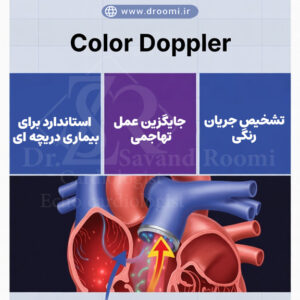

تصویر آموزشی که تفاوت دریچه سالم و دریچه دارای نارسایی را با جریان خون رنگی نشان میدهد.

چرا اکو داپلر رنگی به عنوان بهترین روش تشخیص شناخته میشود؟

این تکنیک پیشرفته، که ترکیبی از اکوکاردیوگرافی استاندارد و فناوری داپلر است، نه تنها تصاویر دوبعدی از قلب ارائه میدهد، بلکه جریان خون را به صورت رنگی نمایش میدهد – قرمز برای جریان به سمت پروب و آبی برای جریان دورشونده. این قابلیت اجازه میدهد تا پزشکان مشکلات را با دقت بالا ارزیابی کنند، بدون نیاز به روشهای تهاجمی مانند کاتتریزاسیون. مطالعات متعدد، از جمله تحقیقات منتشرشده در مجلات معتبر مانند Journal of the American College of Cardiology، نشان میدهند که اکو داپلر رنگی برای تنگی آئورت و دیگر اختلالات دریچهای، حساسیت و اختصاصیت بالایی دارد و میتواند حتی regurgitant signals خفیف را در افراد سالم تشخیص دهد. در شیراز، این روش در کلینیک دکتر زهرا سوندرومی توسط بهترین متخصص اکوکاردیوگرافی دریچه قلب شیراز انجام میشود و به بیماران کمک میکند تا برنامه درمانی مناسبی دریافت کنند.

نقش تکنیک داپلر رنگی در نمایش دقیق مشکلات دریچه

تکنیک داپلر رنگی، که بخشی از اکوکاردیوگرافی است، انقلابی در تشخیص بیماریهای قلبی ایجاد کرده است. این روش با اندازهگیری سرعت و جهت جریان خون از طریق امواج صوتی، مشکلات دریچهای را به صورت بصری نمایش میدهد. برای مثال، در اکو رنگی نارسایی دریچه میترال، جریان خون بازگشتی به رنگ آبی یا قرمز ظاهر میشود و شدت آن را میتوان بر اساس اندازه جت رنگی ارزیابی کرد.

مزایای این تکنیک شامل غیرتهاجمی بودن، دقت بالا و قابلیت انجام در مطب است. تحقیقات انجمن قلب آمریکا (AHA) نشان میدهد که داپلر رنگی در تشخیص regurgitation valvular در بیش از ۸۰ درصد موارد دقیق است و حتی در افراد سالم، سیگنالهای خفیف را شناسایی میکند تا از تشخیصهای اشتباه جلوگیری شود. در مقایسه با روشهای قدیمیتر مانند اکوکاردیوگرافی ساده، داپلر رنگی اطلاعات دینامیکی بیشتری ارائه میدهد و برای ارزیابی نارسایی دریچه قلب با اکو رنگی ایدهآل است.